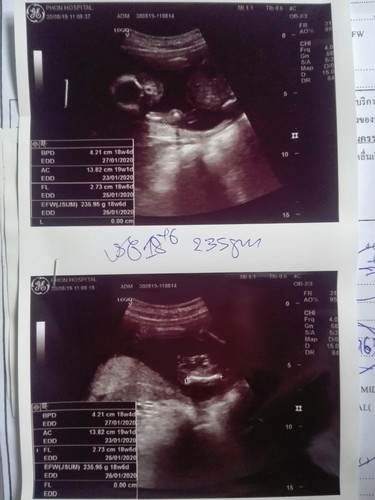

ได้ลูกสาว?

หมอดูตรงไหนว่าได้ลูกสาวค่ะ ใครดูออกบ้าง เราดูไม่ออกเลยจ้า?

ดูยากจังเลย แต่ยินดีด้วยนะคะ

กำลังตั้งครรภ์